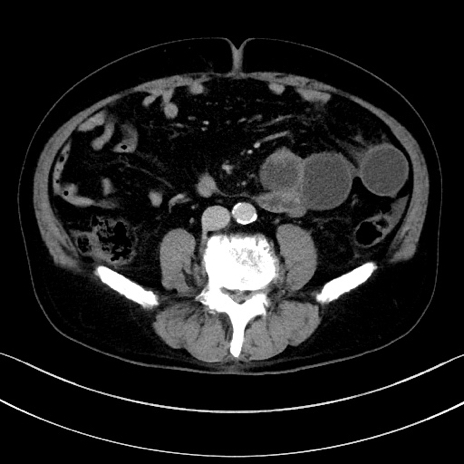

症例15(横断像)

【症例】70歳代男性

【主訴】腹痛

【現病歴】今朝から腹痛あり。全体的に痛い。特に左上の方。排ガスが今日はない。冷や汗が出る。

【既往歴】直腸癌術後

【身体所見】左側腹部〜上腹部に圧痛あり。腹膜刺激症状明らかなではない。軽度反跳痛。左下腹部に術後瘢痕あり。

【データ】WBC 7700、CRP 0.02